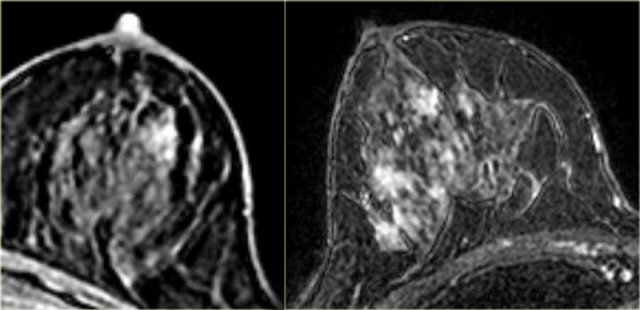

The image on the far left is of a diffuse invasive lobular carcinoma.

On the right is a MIP showing a large area of abnormal enhancement, which proved to be a diffuse invasive lobular carcinoma.